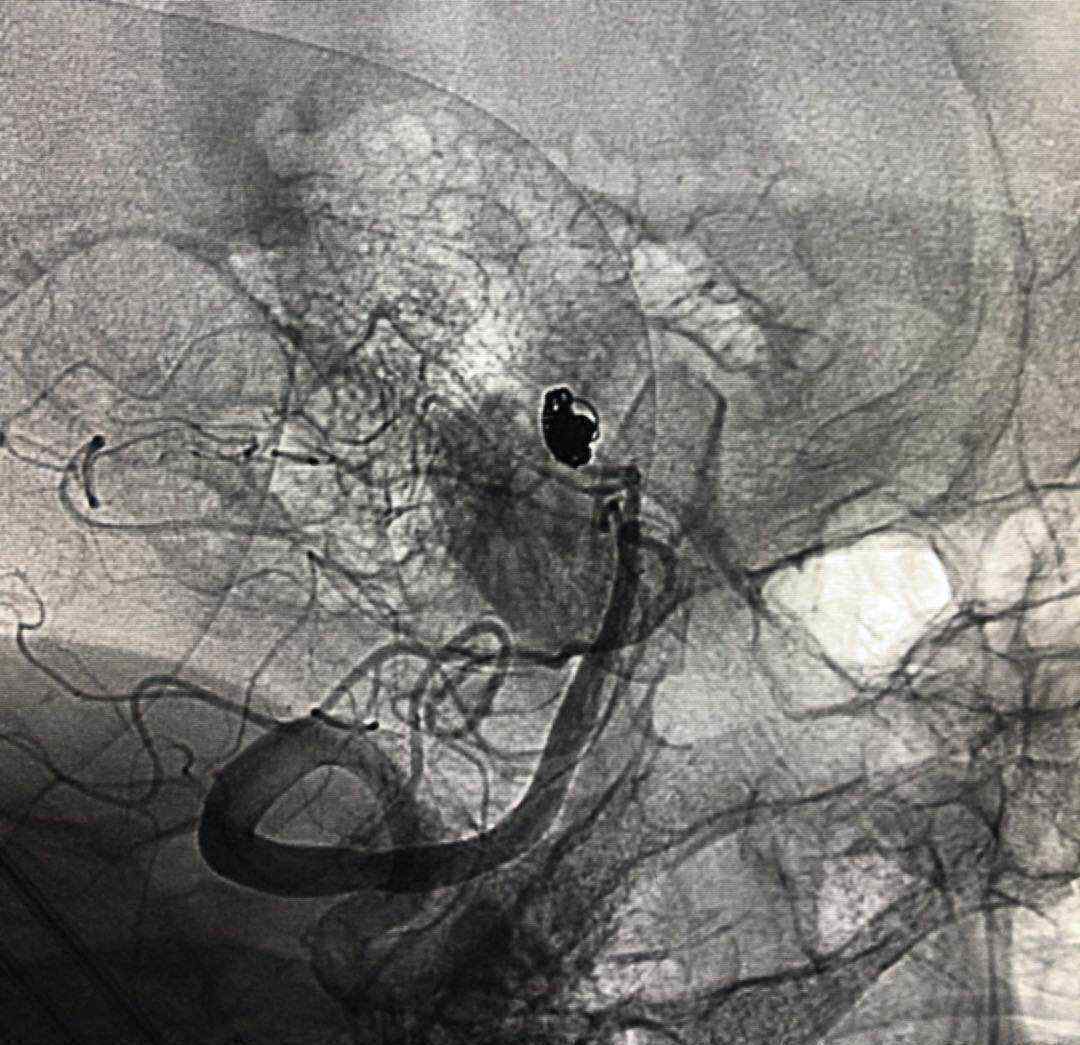

入院后行CTA,考虑左侧后交通动脉瘤。但局部高密度影,考虑动脉瘤破裂出血或巨大动脉瘤附壁血栓可能性大。

考虑为宽基底4.9毫米,大小约为7.9*7.1毫米。

于2019.4.18日行颅内动脉瘤栓塞术